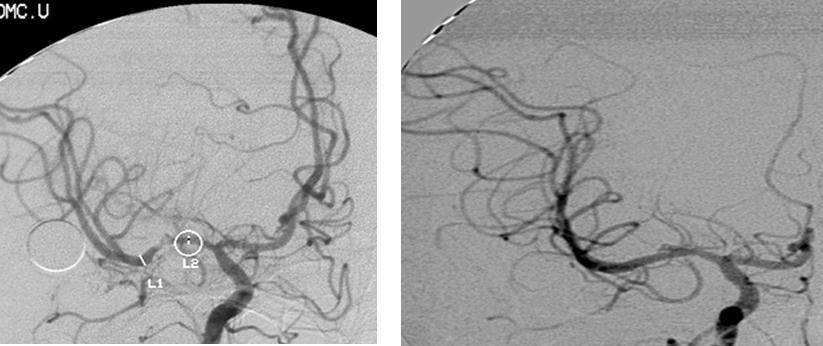

A twenty-nine-year-old female was admitted in Feb, 2006 because of episodic left limb numbness and weakness for half a year. The duration of the episode lasted for a few minutes, seldom over ten minutes. There was an attack every several days. She denied special medical history. She did not live in the pandemic area of Leptospirosis. Her blood pressure was 110/65mmHg and body weight was 51 kilograms. Physical examination found no abnormality. Magnetic resonance angiogram (MRA) (Feb 22) showed severe stenosis in the M1 segment of right MCA. In the source images of MRA, an oval area of abnormal signal in the right basal ganglion was found (Figure 1). Blood routines, coagulation tests, blood biochemistry tests, and C-reactive protein level were normal. The anti-nuclear antibody (ANA), anti-extractable nuclear antigen (ENA) antibodies, and anti-neutrophil cytoplasmic antibodies (ANCA) were negative. Serologic test for Syphilis was negative. Blood sedimentation rate (ESR) was 20 mm/h, and the level of anti-streptolysin O microtitration test (ASO) was 395 IU/ml (0-200 IU/ml). Digital subtraction angiography (DSA) detected severe stenosis (95%) in M1 segment of the right MCA, and the distal blood flow was compromised (Figure 2). The patient was given aspirin 100mg/d, clopidogrel 75mg/d and atorvastatin 20mg/d since Feb 26. Due to the finding of high ASO level, she was given penicillin (4 million IU, bid) for a week. Because of disagreement between the consulting physician and the interventional radiologist, her angioplasty and stenting was delayed till Mar 21 on her request. During the waiting time, her attacks did not reduce. Before the operation, besides the combination of aspirin and clopidogrel, subcutaneous low molecular weight heparin (LMWH) (5000U, q12h) was given for 5 days. After a complete diagnostic evaluation of the blood vessels with DSA, stenting was performed with a stainless steel stent 2.75 mm in diameter by 1.5 cm in length (PC, Abott Company) at the presure of 7 atm. No compromise of perforating branches was found and residual stenosis was less than ten percent on angiography (Figure 2).

Figure 2.Right MCA before and after angioplasty and stenting

Right MCA before and after angioplasty and stenting

Figure 4.CTA image

CTA image

The right MCA stenosis, which led to the transient ischemic attack (TIA) symptoms, was definitely diagnosed. Angioplasty and stenting was conducted after full preparation of dual anti-platelet therapy. Immediately before the operation, LMWH was used in combination and was continued after operation. Her condition was stable in the first two days after operation. Then crescendo TIA recurred and led to motor impairment. Two lesions were shown in the emergent CT images. One was near the anterior horn of the right lateral ventricle, by which it was difficult to explain the symptoms and physical signs. The other was in basal ganglia, and was related to the symptoms and signs. The signal in this region had been slightly higher than the counterpart in the left in the source image of MRA before operation. Hence the lesion in basal ganglia was thought to result from hemodynamic impairment in distal parts of stenotic MCA. Both lesions had clear boundaries, which indicated that the infarction in the area supplied by deep branch of MCA occurred before the TIA attacks. The crescendo TIA worsened gradually, but got partial recovery after volume expansion treatment initially. TCD test showed the blood flow velocity increased in both ACA, especially in the right, while that in the right MCA did not significantly increase. This indicated that some collateral circulation had formed, to counteract hypoperfusion caused by progressive stenosis in the right MCA. Based on these, we deduced that there was IST which did not completely block the right MCA. The symptoms and physical signs appeared again when there was failure of collateral compensation. Because there were new lesions on CT scan and the patient had been treated with dual anti-platelet treatment and anticoagulation, thrombolytic therapy could not be given. So we gave unfractionated heparin (UFH). The symptoms and physical signs disappeared on the next day. But two days later during the same treatment, the symptoms and signs recurred, volume expansion was ineffective, this indicated that initial recovery of symptoms was due to compensatory collateral circulation, and anticoagulation therapy with UFH may also play a role. But this could not prevent thrombosis from progressing, so we increased the dose of anticoagulation drugs, the symptoms and signs disappeared eventually. CTA (Apr 3) and repeated TCD (Apr 17) confirmed our reasoning with attenuated proximal lumen of right MCA and increased blood flow velocities of the right MCA and ICA.